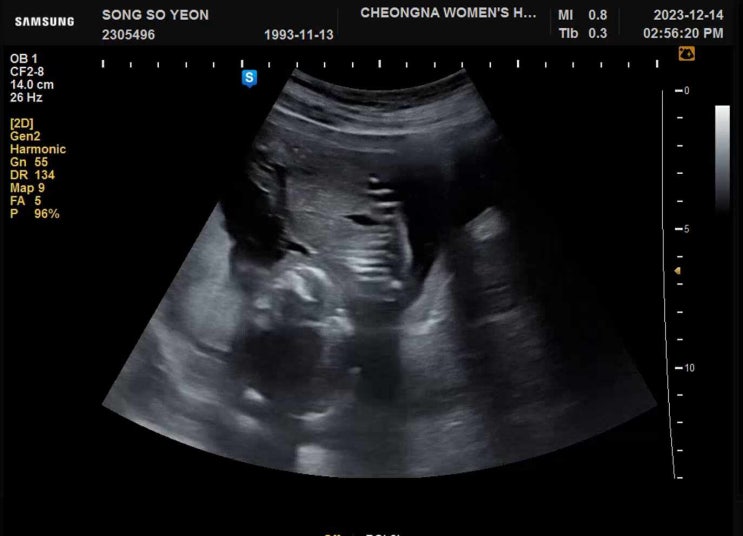

다솜이 첫만남

9/16일 첫만남 한번의 유산 다시 만난 소중한 아가 아프지말고 건강하게만 태어나다오 “애틋하게 사랑하는...

다솜이

12/14